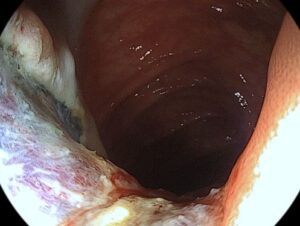

Ασθενής 69 ετών προσήλθε στην Ενδοσκοπική μονάδα Πειραιά για προγραμματισμένη κολονοσκόπηση και αφαίρεση πολύποδων παχέος εντέρου . Ο ασθενής υπεβλήθη σε κολονοσκόπηση από τον Διευθυντή της Ενδοσκοπικής Μονάδας, Δρ Σταύρο Καρακατσάνη. H εξέταση πραγματοποιείται με τελευταίας τεχνολογίας ενδοσκόπιο (PentaxImagina) FullHighDefinition και με χρωμοενδοσκόπηση (i–scan). Κατά την κολονοσκόπηση αφαιρέθηκαν με ενδοσκοπική πολυπεκτομή οι κάτωθι πολύποδες:

Εγκάρσιο :Επανελέγχεται η γνωστή επίπεδη πολυποειδής βλάβη διαμέτρου 4εκ., αφαιρέθηκε με βρόχο πολυπεκτομής μετά από υποβλεννογόνια έγχυση BluedeMethylene. Στη συνέχεια έγινε θερμοκαυτηριασμός στα ορατά αγγεία με Argon Plasma Coagulation (APC). Τοποθετήθηκαν 12 μεταλλικά αιμοστατικά clipsγια την σύγκλιση του ελλείματος και την αποφυγή μεταγενέστερης αιμορραγίας.